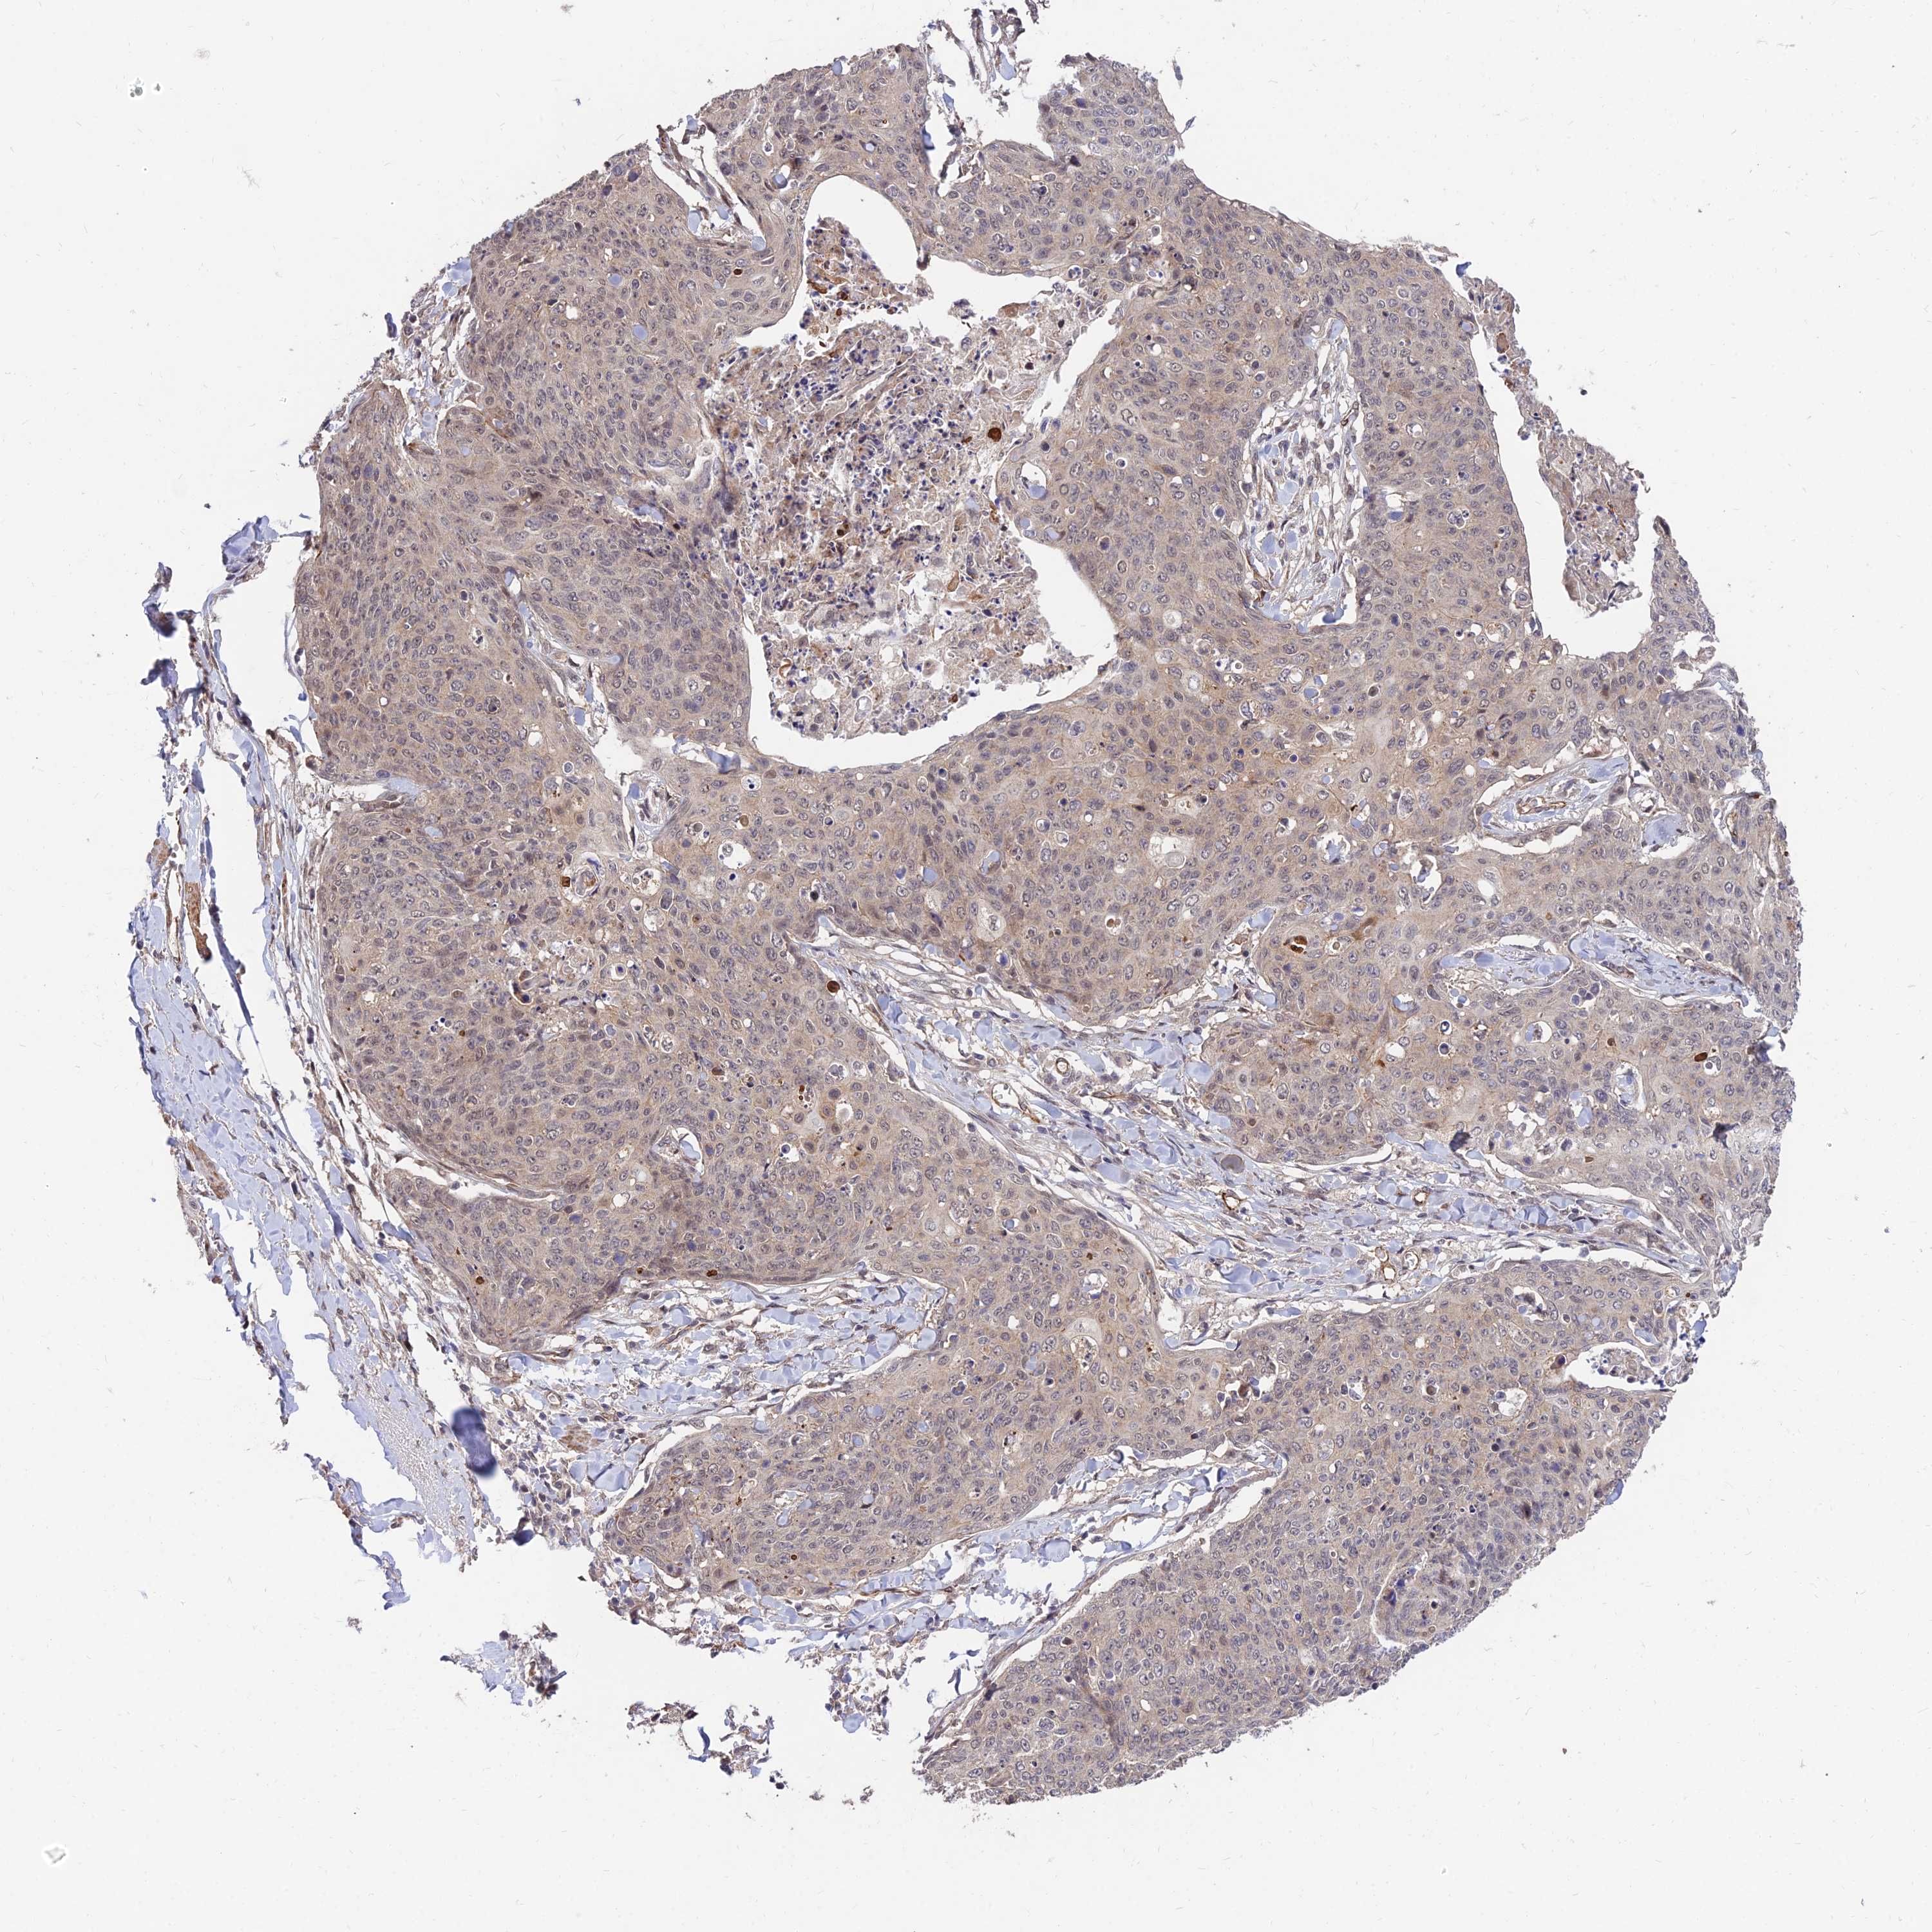

Basal cell and squamous cell cancer

SKIN CANCER - Protein expressioni

A mouse-over function shows sample information and annotation data. Click on an image to view it in a full screen mode. Samples can be filtered based on level of antibody staining by selecting one or several of the following categories: high, medium, low and not detected. The assay and annotation is described here.

Antibody HPA044760

Staining

High

Intensity

Strong

Quantity

>75%

Location

Nuclear

Basal cell carcinoma

Squamous cell carcinoma, NOS

Squamous cell carcinoma, metastatic, NOS